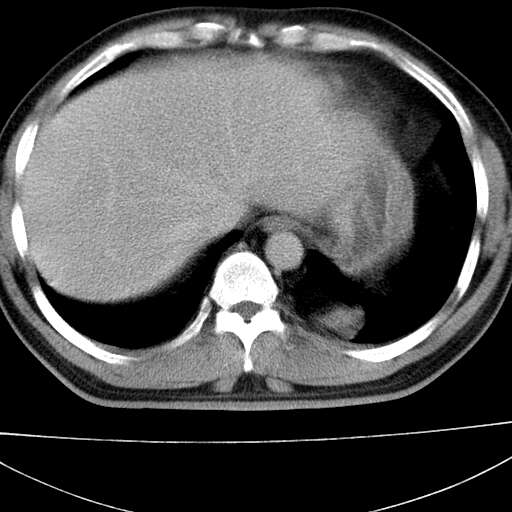

标题: CT21921:腹膜后腔肿物。患者男39Y。体检。增强扫描时间欠准

左侧膈肌脚外缘见一结节样软组织影,密度较均匀,与胸膜关系稍密切,增强轻度强化;考虑来自胸膜良性病变(胸膜纤维瘤可能)。建议加扫胸部ct检查。

2、左下膈肌脚外缘结节状病变,与胸膜交界面呈锐角,胸膜下脂肪线可见,定位于肺内,考虑支气管囊肿或肺隔离征可能性大。

左膈肌角后腹膜腔见肿物影,其内见脂肪密度灶及软组织密度灶,强化不明显。病灶大部在后腹膜内。考虑异位嗜铬细胞瘤或脂肪肉瘤、畸胎瘤